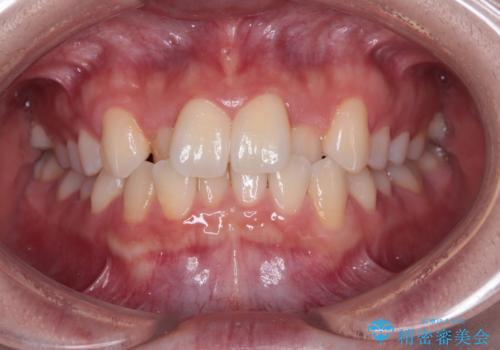

受け口と八重歯を改善 インビザライン矯正治療